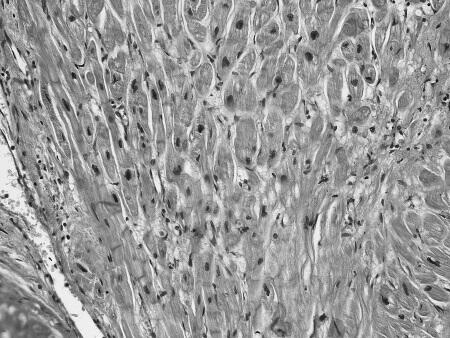

Что же общего среди всех этих состояний и что определяет их патогенетическую взаимосвязь с ФП? Очевиден механизм нарушения электрических процессов в результате ремоделирования миокарда. Данные патологоанатомических исследований подтверждают это. Так, при гистологическом исследовании ткани предсердий умерших пациентов с ФП часто выявлялись следующие изменения (см. рис. 5):

дистрофические изменения кардиомиоцитов, гипертрофия кардиомиоцитов (см. рис. 5 а б);

а)

б)

Рисунок 5.Гистологические изменения предсердий при ФП